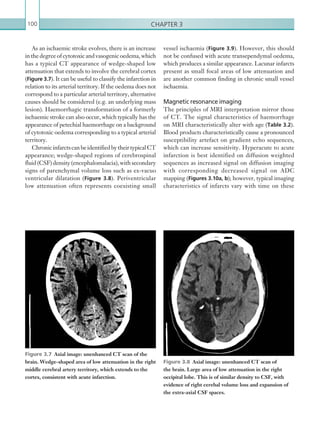

pulmonary embolism: increasing the model’s utility with the SimpliRED D-dimer. Thromb Haemost 83:416–420, with permission.

DVT = deep pain thrombosis; PE = pulmonary embolism.